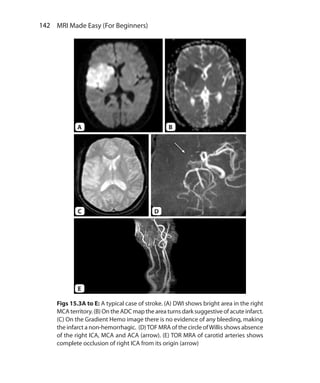

required to null the signal from a tissue is 0.69 times T1 relaxation

time of that tissue.

Types of IR Sequences

IR sequences are divided based on the value of TI used. IR sequences

can be of short, medium or long TI.